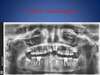

Couronnes fixes scellées